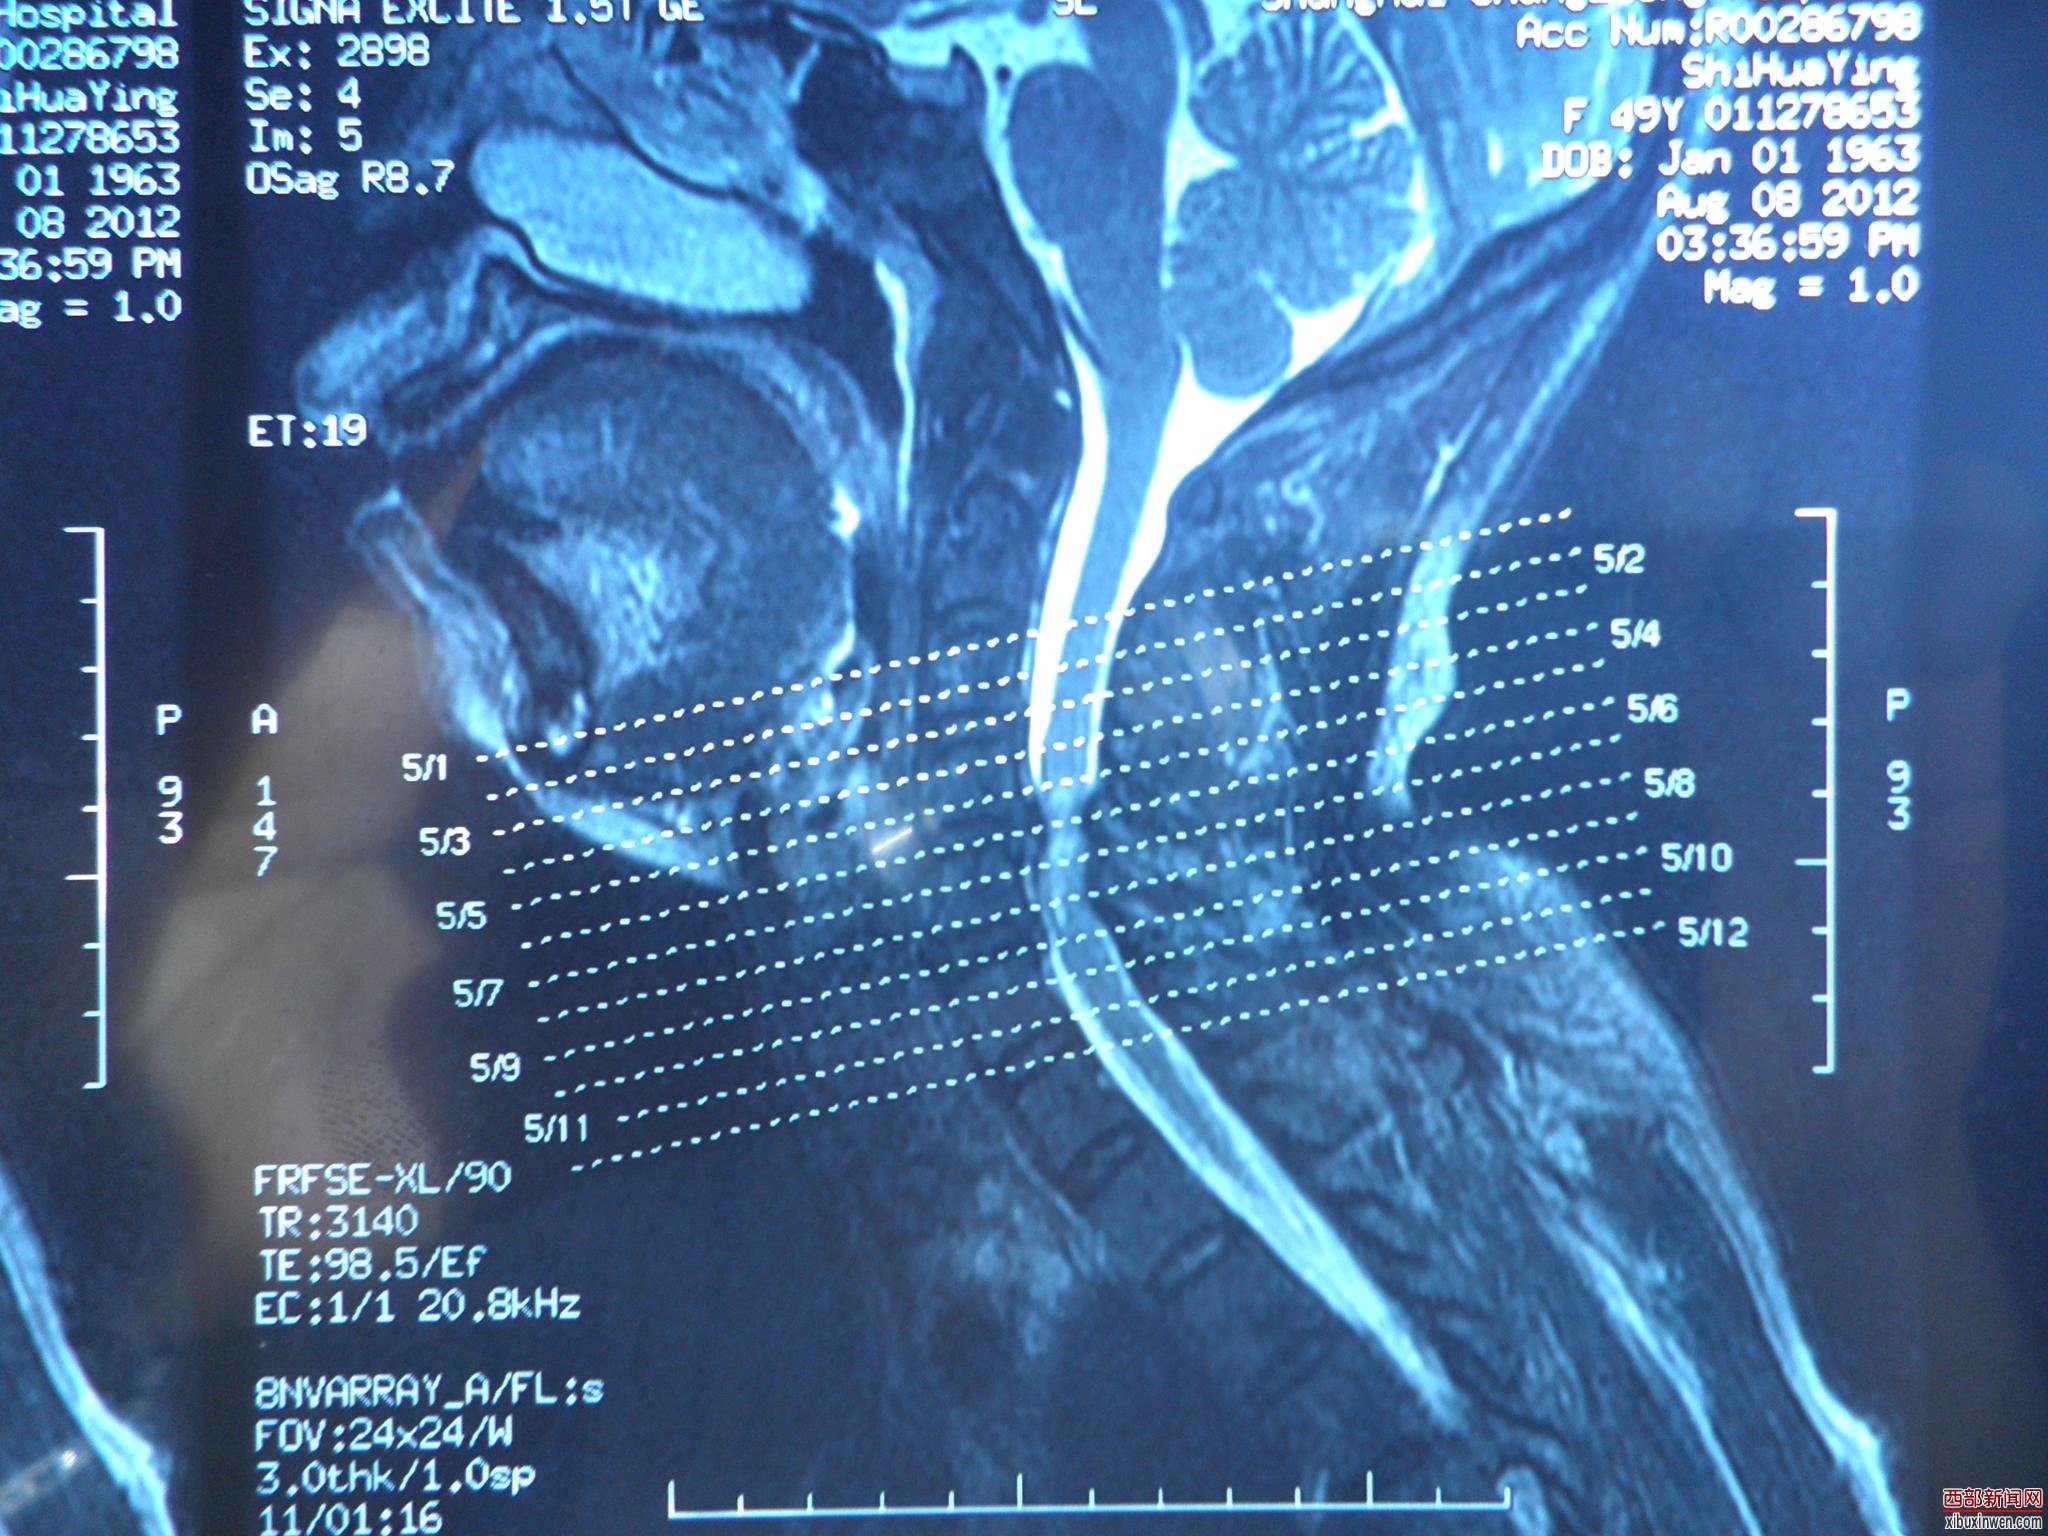

2012年8月8日,我妈摔成高位截瘫,转送多家医院,后送至上海市长征医院,医院的片子出来后,所有的医生都紧张:照片子的情况来看,我妈的第四第五根颈椎粉碎性骨折并把中枢神经给压死了一段。医生说:如果桑兰能站我妈妈就能站,除非有奇迹!我和我爸都崩溃了。还说:我妈的神经已经死了一部分,神经死了是不会恢复的。于8月13日经骨科袁文、陈华江、曹鹏、祁敏等医生做了植骨固定术,当时长征医院的住院号515317。

附上病人的损伤片子(所拍时间2012年8月8日)